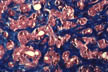

Biliary fibrosis

Fig.73 - BILIARY FIBROSIS: Portal area with marked ductular proliferation and minimal inflammation in a case of chronic biliary obstruction. To be distinguished from cirrhosis.